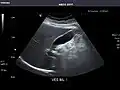

Liver

Ultrasonography of the liver with some standard measurements[6]

In patients with deranged liver function tests, ultrasound may show increased liver size (hepatomegaly), increased reflectiveness (which might, for example, indicate cholestasis), gallbladder or bile duct diseases, or a tumor in the liver.

Ultrasonography of liver tumors involves two stages: detection and characterization. Tumor detection is based on the performance of the method and should include morphometric information (three axes dimensions, volume) and topographic information (number, location specifying liver segment and lobe/lobes). The specification of these data is important for staging liver tumors and prognosis. Tumor characterization is a complex process based on a sum of criteria leading towards tumor nature definition. Often, other diagnostic procedures, especially interventional ones, are no longer necessary. Tumor characterization using the ultrasound method will be based on the following elements: consistency (solid, liquid, mixed), echogenicity, structure appearance (homogeneous or heterogeneous), delineation from adjacent liver parenchyma (capsular, imprecise), elasticity, posterior acoustic enhancement effect, the relation with neighboring organs or structures (displacement, invasion), vasculature (presence and characteristics on Doppler ultrasonography and contrast-enhanced ultrasound (CEUS).